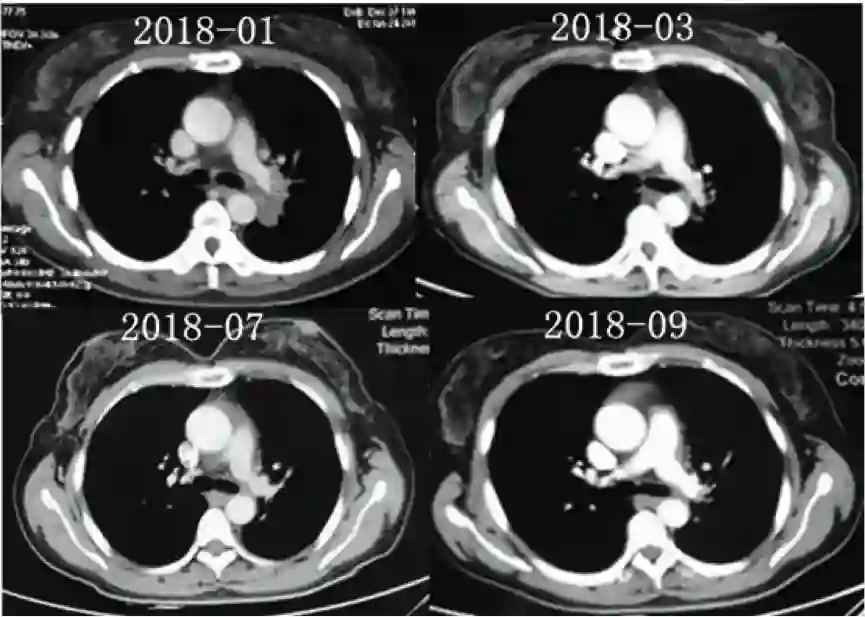

患者诊断IVA期伴ALK阳性,故于2018年2月开始克唑替尼治疗,治疗过程耐受性良好,疗效评价PR。并且患者于2018年9月因腰骶部疼痛行骶骨转移灶放疗。

图4.患者接受克唑替尼治疗时候的基线情况(2018-01)、以及治疗随访胸部CT影像